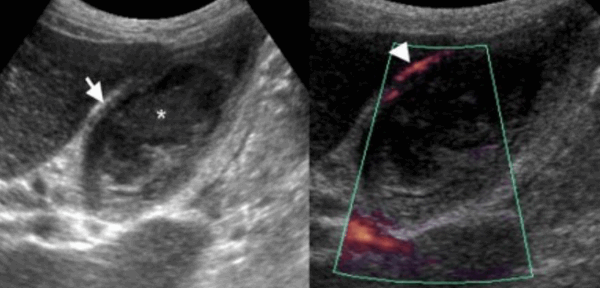

УЗИ некалькулезный холецистит.

74 — летнему мужчине выполнено УЗИ желчного пузыря. Диагноз: острый некалькулезный холецистит. На левой сонограмме стрелкой указано утолщение стенок желчного пузыря. В просвете желчного пузыря взвесь. На правой сонограмме у того же пациента при исследовании в доплеровском режиме выявлен еще один признак воспаления — гиперемия.